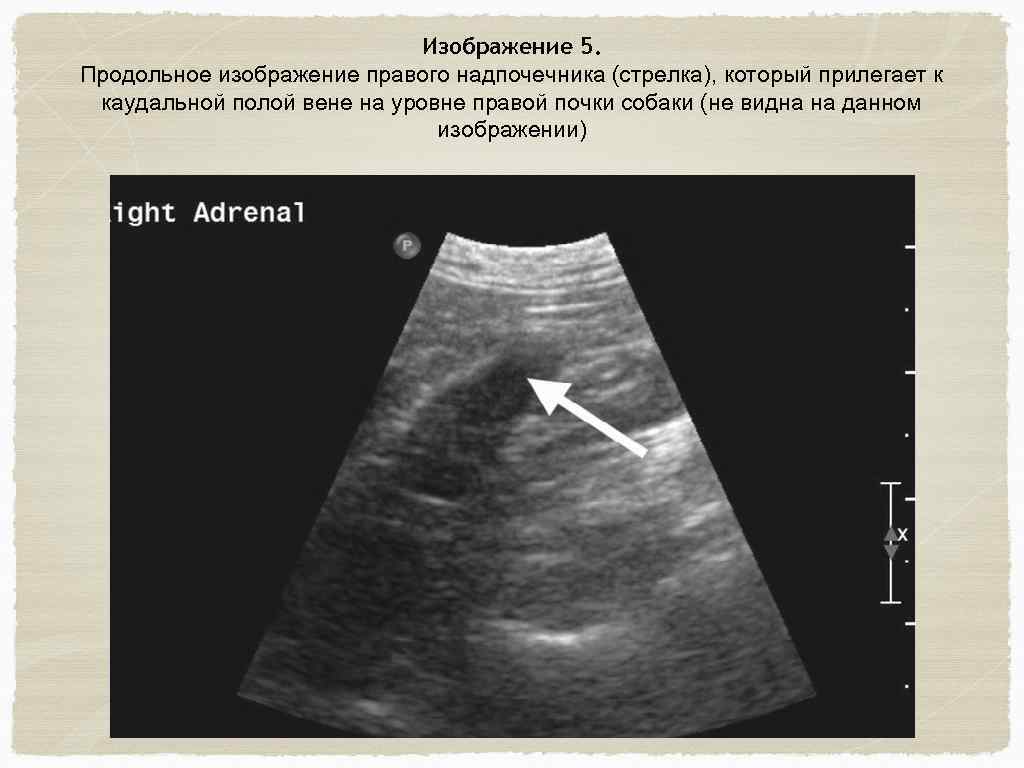

Правая почка и правая надпочечная железа Датчик должен быть расположен по длинной оси. Необходимо следовать вдоль каудальной полой вены по правой стороне живота до уровня правой почки (изображение 3) Затем оценивается правая почка по продольной и поперечной оси. (изображение 4) Угол датчика (по продольной оси) должен располагаться медиально к правой почке. Правый надпочечник находится рядом с каудальной полой веной. (изображение 5) Затем можно оценить правую сторону печени и желчный пузырь. Для точного результата проводить исследование необходимо по часовой стрелке по внешнему кругу.

Изображение 5. Продольное изображение правого надпочечника (стрелка), который прилегает к каудальной полой вене на уровне правой почки собаки (не видна на данном изображении)